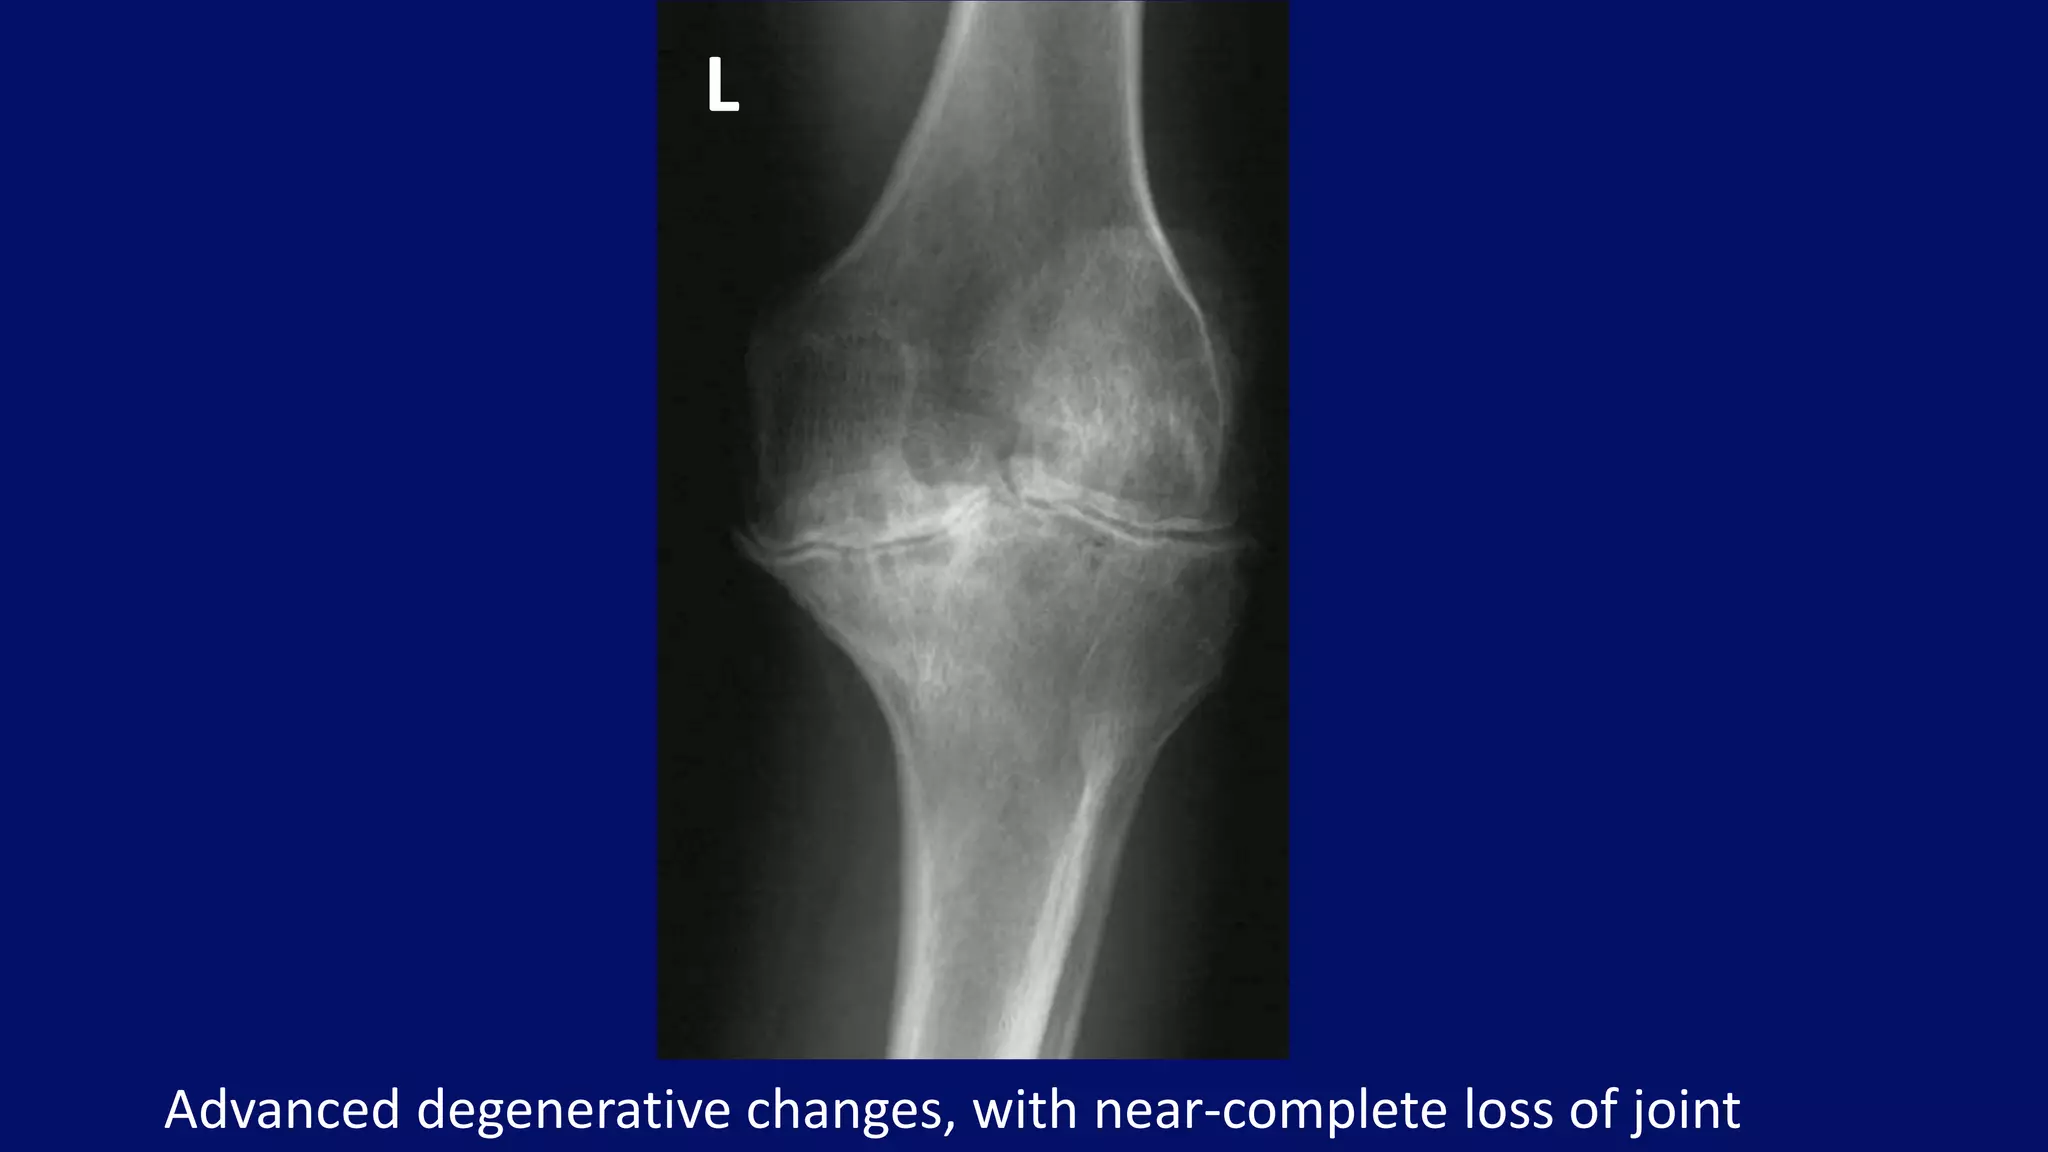

Advanced degenerative changes, with near-complete loss of joint

L